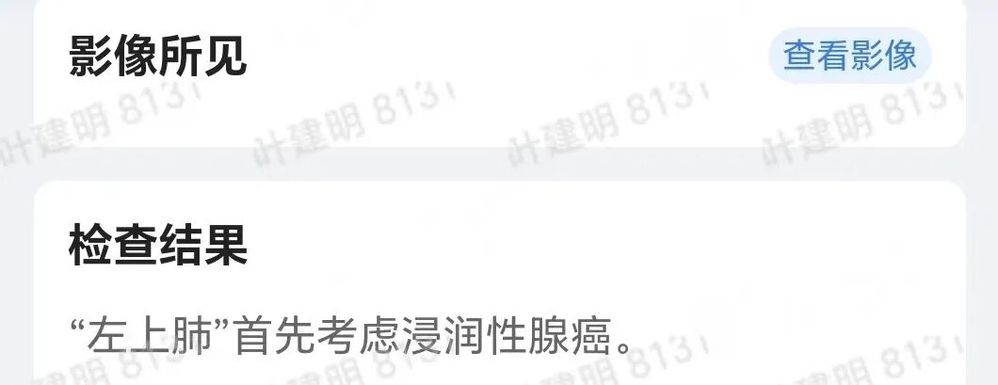

患者于3年余前于某市级医院体检,行胸部CT提示“左上肺斑片影”,予以保守观察,定期复查。今日患者为复查来我院吴山院区门诊就诊,复查2026-03-03 肺结节CT靶重建+结构化报告(吴山):靶结节 1,左肺上叶条片状稍高密度影,肿瘤性病变考虑,请结合临床病史并与原片对比、结合肺结节门诊意见。靶结节 2,右肺上叶(SE4,IM85)结节,考虑AIS或MIA,请结合肺结节门诊意见。余肺内小结节,建议6个月复诊,LUNG-RADS 2-3。患者现无明显不适,为求进一步诊治,拟“肺部阴影”收入我科。 患者起病以来,神志清,精神可,胃纳可,睡眠安,二便正常,体重近期无明显变化。

2026年3月初年后,由于自媒体上刷到杭州市肿瘤医院叶建明,遂来市肿瘤门诊看。我考虑是肺癌,而且早在2022年时就得高度怀疑,现在明显进展(主要表现为密度增加,实性成分增多)。由于在杭州市一医院系统没有影像资料,为了术中可能需要看影像,建议查次CT,所以索性做了靶扫描重建。

杭州市肿瘤医院影像展示与分析: